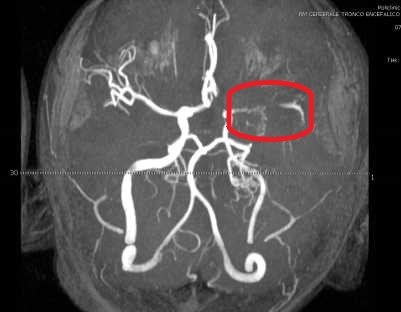

Il giorno successivo ritorna in Accettazione per il peggioramento della sintomatologia. La RM encefalo urgente descrive: “Nella sequenza angio-RM arteriosa intracranica l’arteria carotide interna sinistra dal tratto cervicale distale sino al sifone carotideo ha calibro uniformemente ridotto rispetto alla controlaterale senza segni di dissezione recente, l’arteria cerebrale media di questo lato si visualizza nel tratto M1 prossimale di aspetto sottile e nel tratto M1 distale non si osserva flusso, presenza di sottili strutture vascolari tortuose nella scissura silviana adiacente, i rami di divisione dell’arteria cerebrale media a valle sono assottigliati rispetto ai controlaterali; i reperti sono suggestivi di un quadro Moyamoya-like” (Figure 1 e 2).

Il ragazzo veniva pertanto ricoverato presso il nostro reparto, dove è stata iniziata terapia con acido acetilsalicilico (150 mg x 2 per i primi 4 giorni; successivamente 150 mg una volta die), ed è stata eseguita una angiografia cerebrale che confermava la stenosi a carico del tratto prossimale dell’arteria cerebrale media e la presenza di circoli collaterali di compenso, confermando così il quadro di Moyamoya-like.